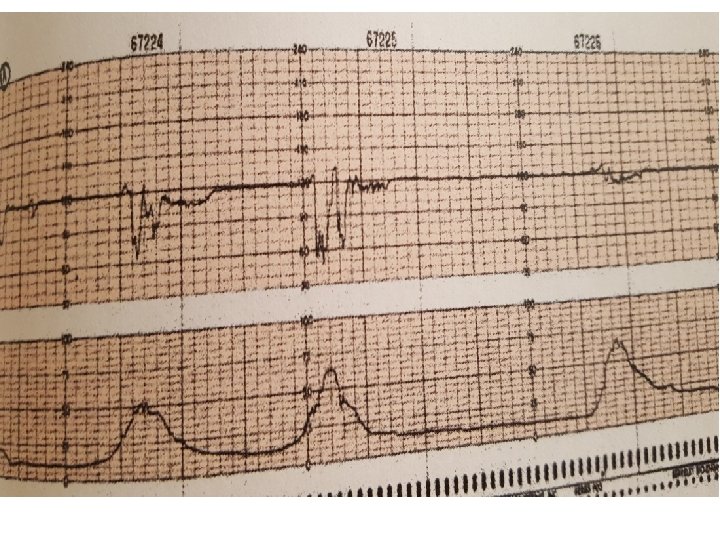

Variable Deceleration Typical: • shoulders Atypical : • Overshoot • Loss of primary shoulder • Slow return to baseline (late component) • Baseline returns to a lower level(after deceleration) • Biphasic(W shape) • loss of variability during deceleration

Complicated variable deceleration Indicated fetal hypoxia • Tachycardia • Lack of variability • Slow return to baseline • Large amplitude(to 60 bpm or duration 60 second) • Loss of pre and post shouldering • Smooth overshoot

variable decelerations with absent to minimal variability

Variable decelerations with minimal to absent variability